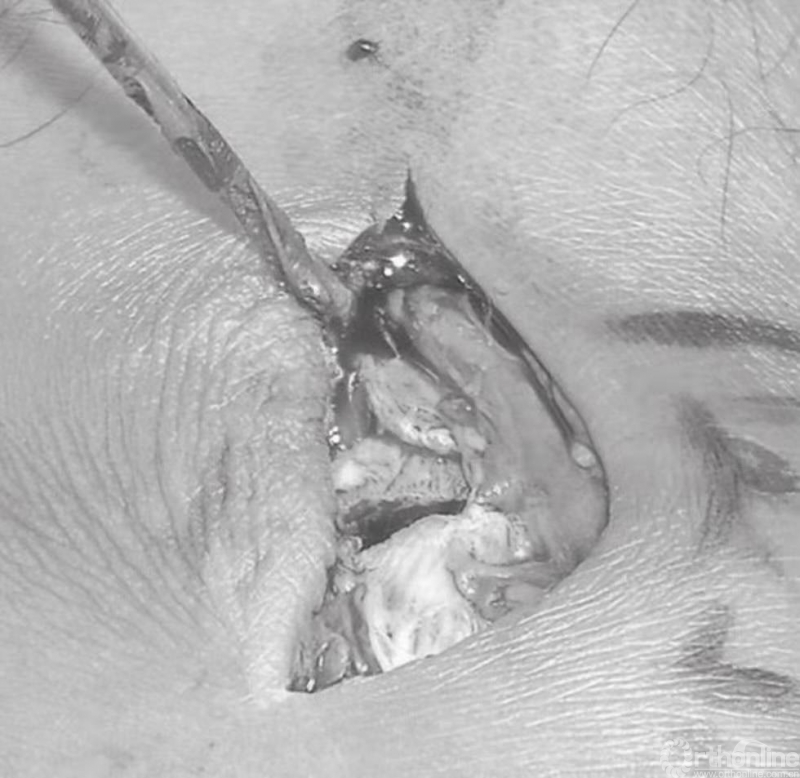

内踝骨折中通常会伴有骨膜撕裂(图11)。这些骨折病例大多数均存在骨膜的介入,这便造成了愈合困难,可能导致骨不连。应将骨膜抬离骨折端,并清理折断表面的血块。将骨折片向远端回缩,以观察关节。在移除关节内所有的游离骨块后,用盐水清洗关节(图12)。

图12 在移除关节内所有的游离骨块后,用盐水清洗关节